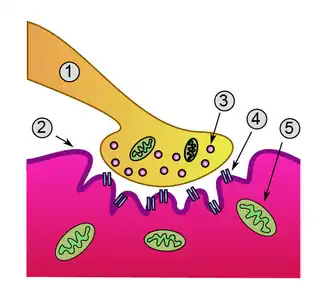

Нервно-мышечный синапс

2. Сарколемма

3. Синаптический пузырек

4. Никотиновый ацетилхолиновый рецептор

5. Митохондрия

Нервно-мышечный синапс (также нейромышечный, либо мионевральный синапс) — нервное окончание на скелетном мышечном волокне. Входит в состав нервно-мышечного веретена. Нейромедиатором в этом синапсе является ацетилхолин.

В этом синапсе нервный импульс превращается в механическое движение мышечной ткани.

В нервно-мышечной системе нервы центральной нервной системы и периферической нервной системы связаны и работают вместе с мышцами[1]. Нервный отросток подходя к сарколемме мышечного волокна утрачивает миелиновую оболочку и образует сложный аппарат с плазматической мембраной мышечного волокна, образующийся из выпячиваний аксона и цитолеммы мышечного волокна, создавая глубокие «карманы». Синаптическая мембрана аксона и постсинаптическая мембрана мышечного волокна разделены синаптической щелью. В этой области мышечное волокно не имеет поперечной исчерченности, характерно скопление митохондрий и ядер. Терминали аксонов содержат большое количество митохондрий и синаптических пузырьков с медиатором ацетилхолином.